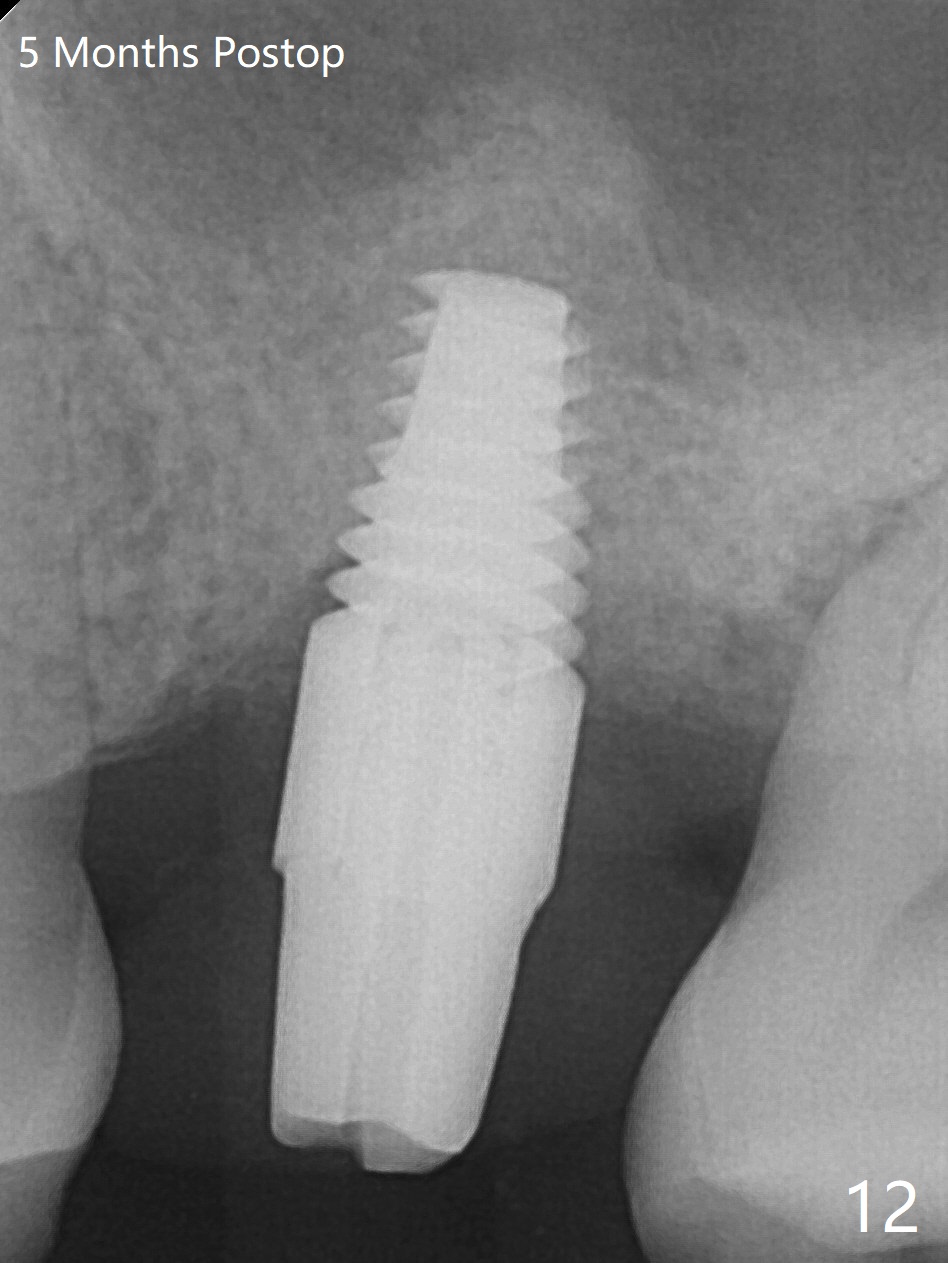

A 65-year-old man had crack tooth syndrome at #14 one month earlier (Fig.1). He shows up with crack and pain in an emergency manner (Fig.2 arrowheads). Preop CT confirms 4.5 mm bone height (Fig.3). Osteotomy will be initiated in the middle of the septum between 3 sockets (Fig.4). Depth of osteotomy is controlled with drill stoppers. After sequential osteotomy free hand, a 5x11 mm tap is used to break through the sinus floor (Fig.5) and sinus lift with Vanilla allograft. To prevent abutment screw loosening, a 5x11 mm tissue-level implant is placed; the distal thread is equicrestal (Fig.6 arrowhead). Following deeper placement of the implant (Fig.7 arrow) with a larger and longer abutment (as compared to that in Fig.6), the margin for an immediate provisional (Fig.9 white curved lines) is prepared in the coronal end of the implant (Fig.8 between arrowheads). With the tissue-level implant, the crown/implant ratio improves. Stress will be partially acting on the implant so that there is less likelihood of abutment screw loosening. The socket heals 1 month postop (Fig.10). The rough surface of the implant is exposed ~ 1 mm. With the margin modified and polished, the provisional returns to place with oral hygiene instruction. It is hoped that the gingiva will cover the exposed rough surface. The buccal rough surface remains exposed 5 months postop (Fig.11). The bone in sinus lift is mature 5 months postop (Fig.12,13). The first 1-2 implant threads are expected to be filled with mature bone in the near future (*). Since the abutment seems long enough for retention, temp bond is used for cementation (Fig.14). Water pik is being applied.